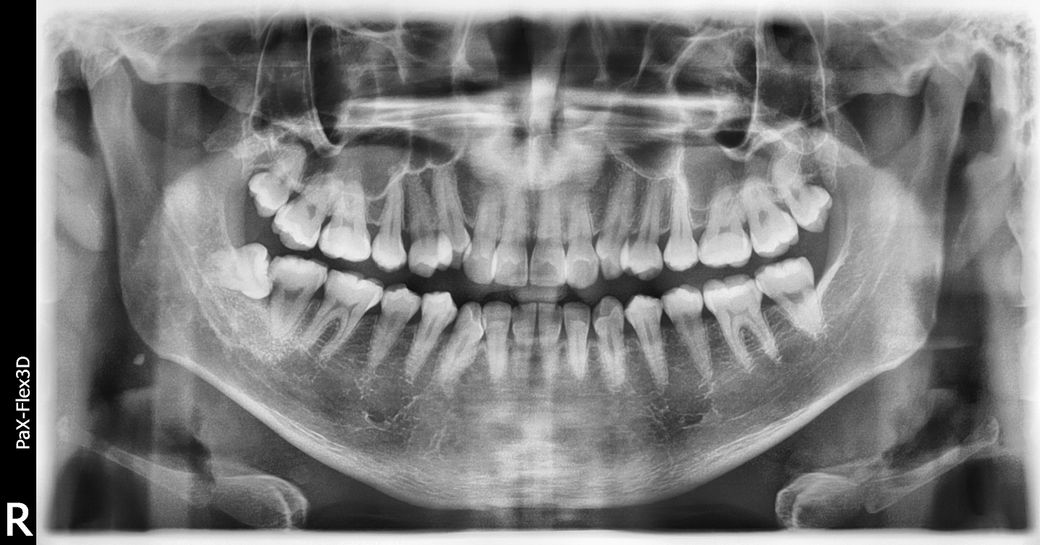

사랑니 옆 어금니 충치 여부를 확인할 수 있는 방안이 있나요?

사랑니를 빼고 의사쌤이 긁더니 딱딱해서 충치가 아닐수도 있다네요. 치경을 사서 해봐도 확인이 어렵습니다. 따로 할수있는 장비나 병원이 따로 있을까요?

사진상으로는 충치가 잇어 보입니다. 하지만 정확하게 보려면 사랑니 발치를 하고나서 확인을 다시 해보셔야될것같습니다.

사랑니 옆 아래 어금니 충치 있어보이는데요 치근단 사진 찍어보면 좀 더 정확히 알 수 있습니다

충치를 진단하는 방법은 여러 가지가 있습니다. 우선 방사선 사진으로 확인을 해볼 수 있으며 육안으로 확인해볼 수 있습니다. 도구로 변색된 부분을 긁었을 때 단단하다면 정지된 충치의 가능성이 높기 때문에 치료가 필요하지 않을 수 있습니다.

자세한 확인을 위해서 치과에서 진료를 받아보는 것을 권유드립니다.